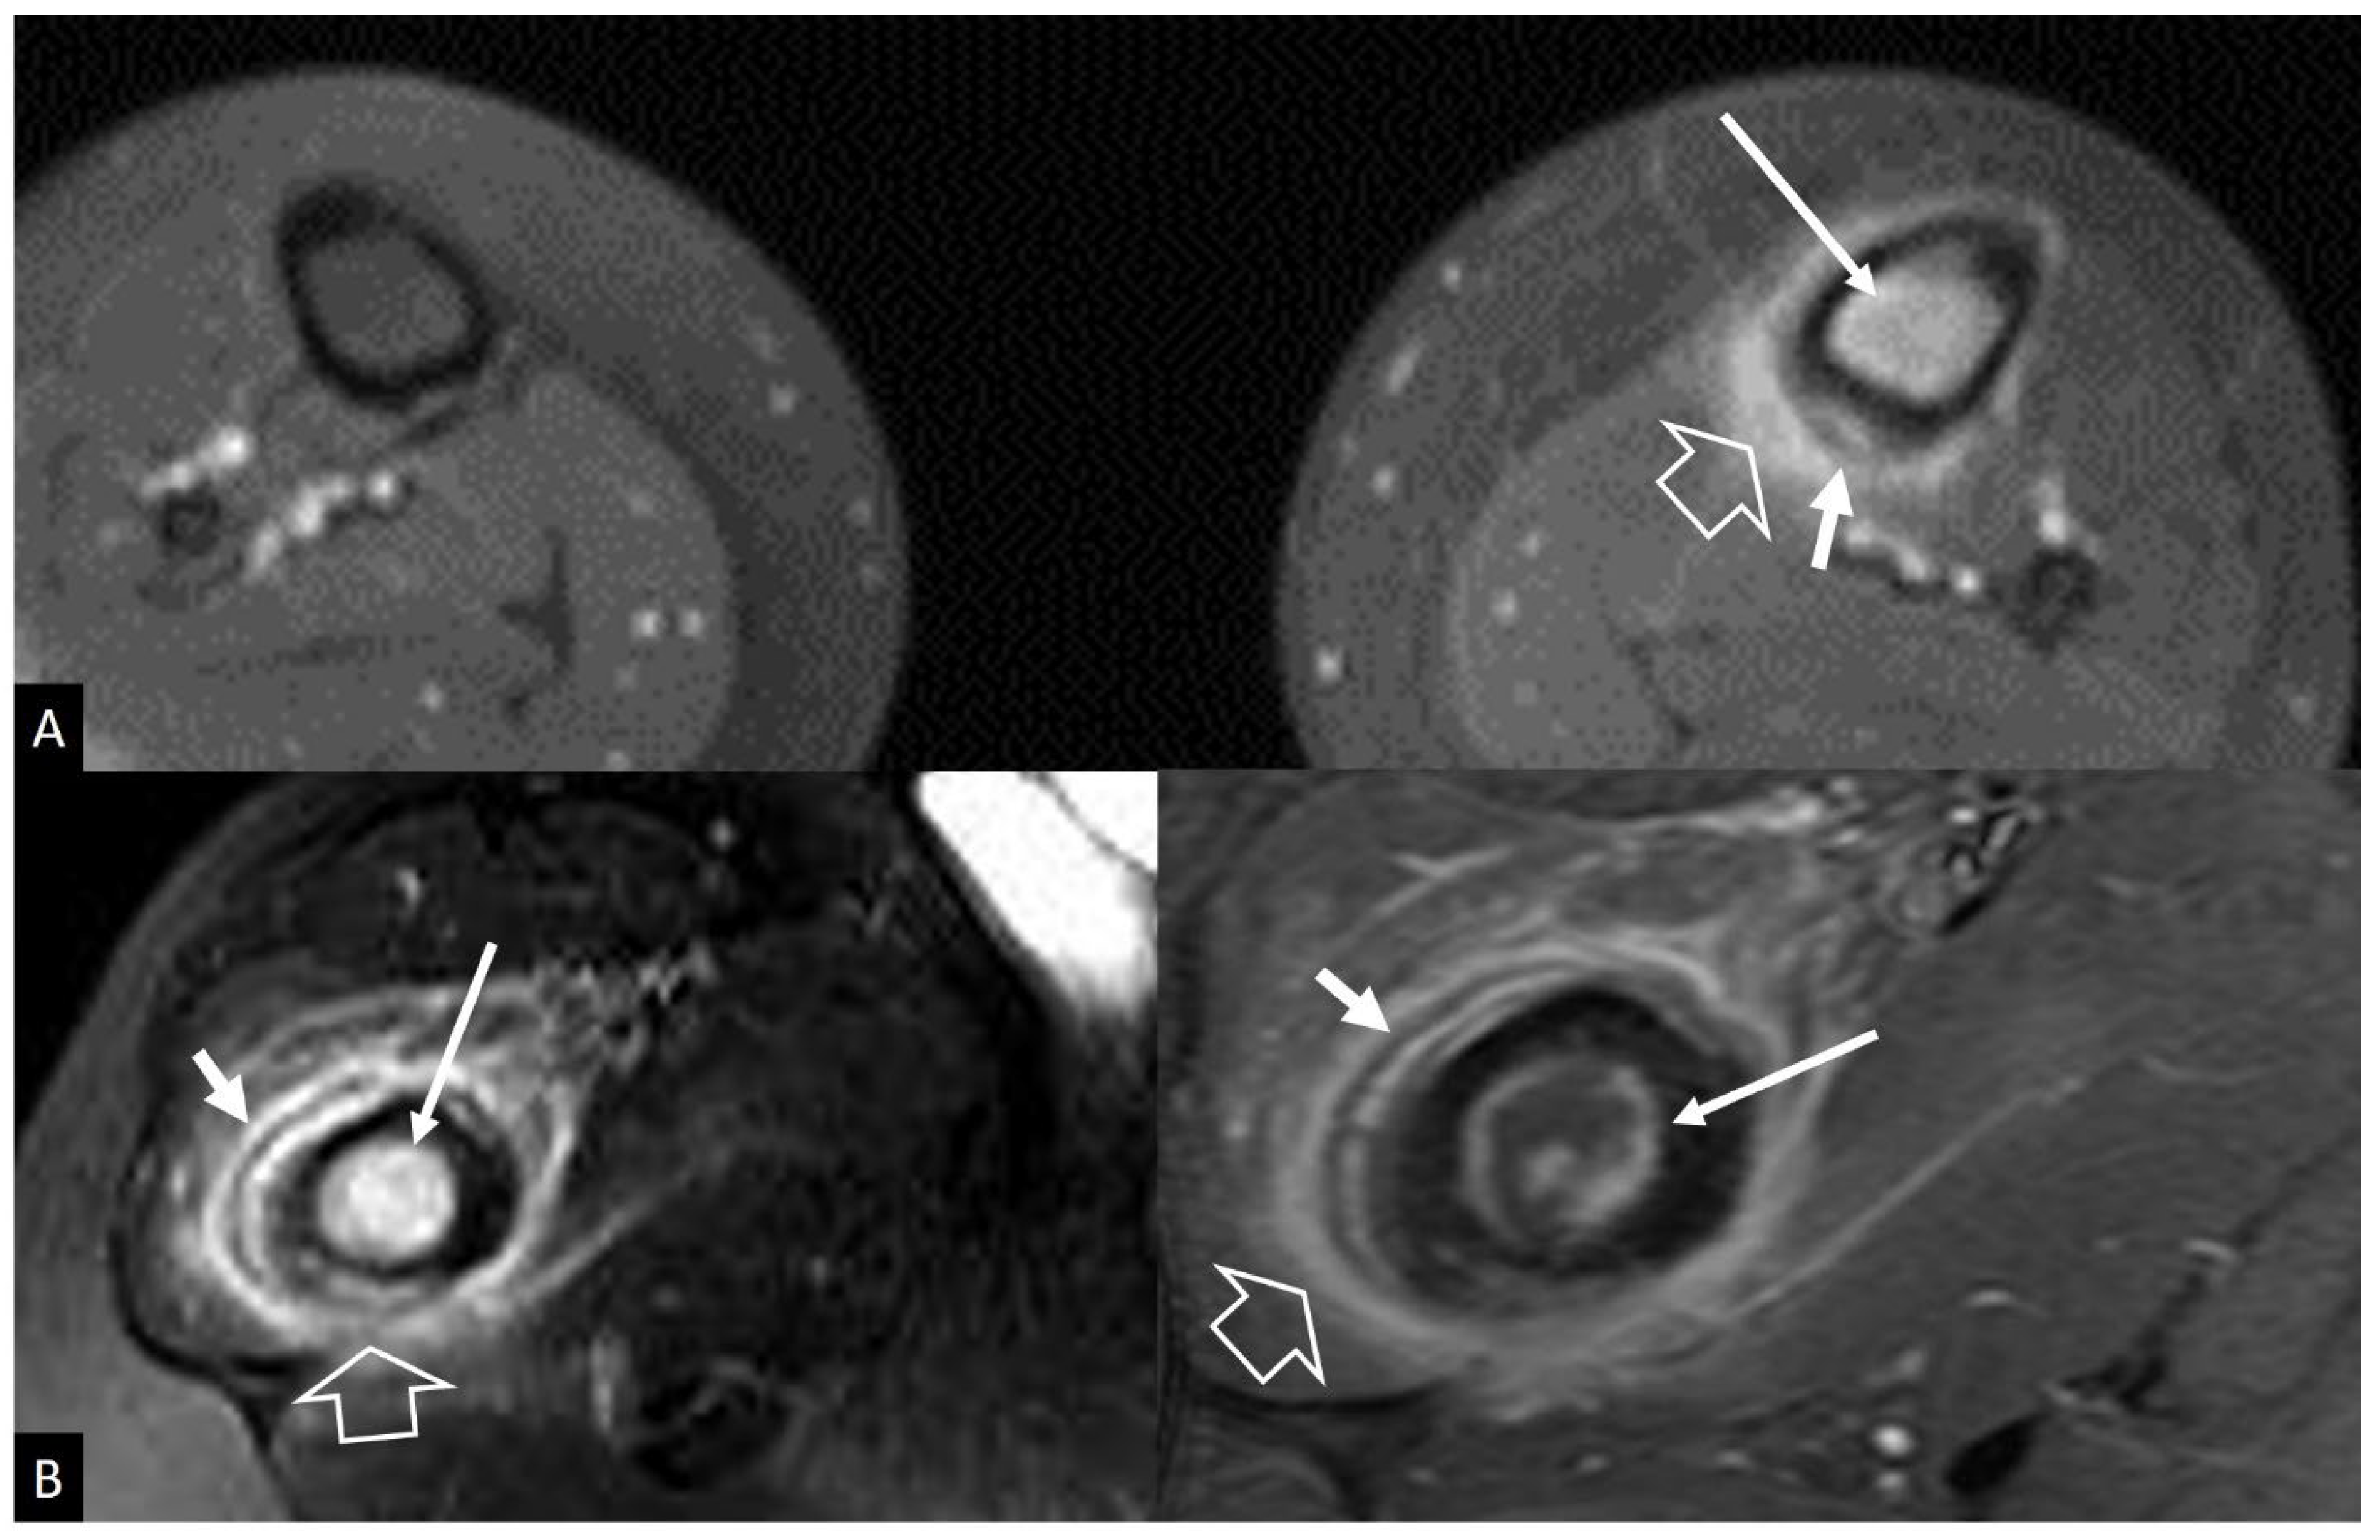

2. b.i. Ewing’s Sarcoma

2. b.ii. Lymphoma

- Henninger B, Glodny B, Rudisch A, Trieb T, Loizides A, Putzer D, Judmaier W, Schocke MF Ewing sarcoma versus osteomyelitis: differential diagnosis with magnetic resonance imaging. Skeletal Radiol 2013, 42, 1097–1104. [CrossRef]

- McCarville MB, Chen JY, Coleman JL, Li Y, Li X, Adderson EE, Neel MD, Gold RE, Kaufman RA Distinguishing Osteomyelitis From Ewing Sarcoma on Radiography and MRI. AJR Am J Roentgenol 2015, 205, 640–650.

- Guermazi A, Brice P, de Kerviler E E, Fermé C, Hennequin C, Meignin V, Frija J Extranodal Hodgkin disease: spectrum of disease. Radiographics 2001, 21, 161–179.

- Majeed A, Chan O, Okolo O, Shponka V, Georgescu A, Persky D Hodgkin Lymphoma Mimicking Osteomyelitis. Case Rep Oncol 2017, 10, 542–547.

- Mika J, Schleicher I, Gerlach U, Adler C-P, Uhl M, Knoeller SM Primary bone lymphomas thought to be osteomyelitis urgently demand a rapid diagnosis in bone pathology. Anticancer Res 2012, 32, 4905–4912.

- Mulligan ME, McRae GA, Murphey MD Imaging features of primary lymphoma of bone. AJR Am J Roentgenol 1999, 173, 1691–1697. [CrossRef]

- Krishnan A, Shirkhoda A, Tehranzadeh J, Armin AR, Irwin R, Les K Primary bone lymphoma: radiographic-MR imaging correlation. Radiographics 2003, 23, 1371–1383. [CrossRef]

- Mulligan ME, Kransdorf MJ Sequestra in primary lymphoma of bone: prevalence and radiologic features. AJR Am J Roentgenol 1993, 160, 1245–1248. [CrossRef] [PubMed]